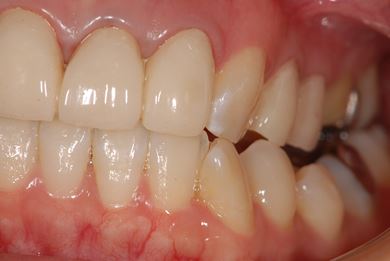

| 性別/年齢 | 女性 / 27歳 | ||||||||||||||||||||||||||||||||

| 主訴 | 審美歯科治療を希望。歯ならびもできるかぎりそろえたい。 | ||||||||||||||||||||||||||||||||

| 治療内容 | オールセラミック4本(オールセラミック用土台4本)、メタルボンドセラミック2本(メタルボンドセラミック用土台2本) | ||||||||||||||||||||||||||||||||

| 総治療費 | 867,825円 | ||||||||||||||||||||||||||||||||

| 治療期間 | 5ヶ月 |